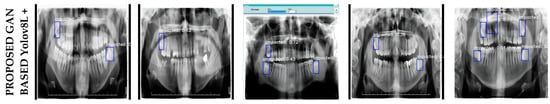

4.2. Limitations

The proposed model is based on the integration of Convolutional Neural Networks (CNN) and transformer-based models on panoramic images enhanced with super-resolution techniques. The ability of the model to accurately detect the location of impacted teeth in all test images clearly demonstrates its overall success and reliability. However, it was observed that the model made errors in some cases, such as misidentifying non-impacted teeth as impacted teeth. Such limitations are critical to better understand the model’s performance in specific scenarios and to identify opportunities for future improvement. To better illustrate the limitations and challenges faced by the model, example images are shown in Figure 4.

Figure 4.

Sample images illustrating the limitations of the proposed model.

The limitations of the model can be clearly seen in images Example-1 and Example-2 in Figure 4. In Example-1, the model incorrectly identified a fractured tooth as an impacted tooth, resulting in a false positive. Similarly, in Example-2, a region with no teeth was incorrectly labeled as an impacted tooth. These cases show that the model can misinterpret some complex structures and produce incorrect results in certain situations. These limitations provide important guidance by highlighting areas where the model needs to be improved. In particular, strategies such as larger and more diverse datasets, integration of more advanced feature extraction methods, and optimization of attention mechanisms could be considered in future studies. Furthermore, techniques to reduce false positive and false negative rates can be applied to make the model more robust in real-world applications.

In conclusion, this study highlights the strengths of the proposed model as well as its limitations, providing important insights that can guide future research. Optimizing the model to address these limitations will provide more effective and comprehensive solutions, not only for impacted tooth detection, but also for other dental detection and analysis problems.